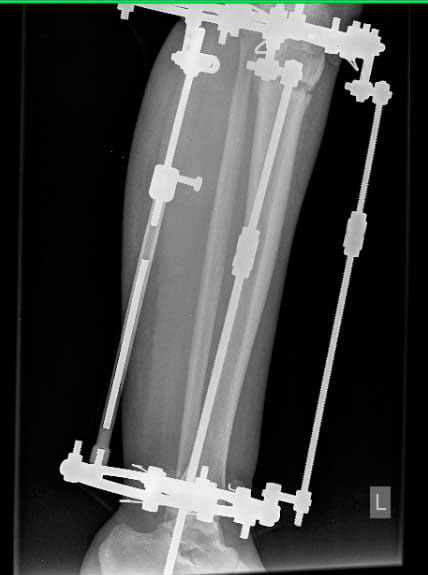

Ножки на сегодня.

20181212_125155.jpg